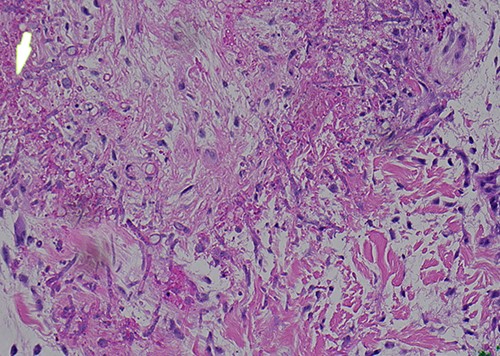

A 58-year-old male with a history of hypertension, hyperlipidemia, asthma, and newly diagnosed Hepatitis C presented with leukocytosis consistent with chronic myelogenous leukemia in blast crisis. He was given hydroxyurea and started on induction 7 + 3 idarubicin and cytarabine chemotherapy. The patient then developed neutropenic fever with multidrug-resistant Escherichia coli bacteremia and VRE enterococcus faecium. After 5 days of neutropenic fever, he developed a ‘knot’ on his left leg (Fig. 1). Physical exam revealed a nontender 1.5 cm violaceous firm indurated papule 2 cm above the left patella without evidence of cellulitis or infection. A total of 2 days later, the patient developed smaller satellite lesions on the left dorsal hand and chest. Dermatology was consulted and performed two 4 mm punch biopsies of the left patellar lesion for tissue staining and culture. Hematoxylin and eosin (H&E) staining revealed an obliterated blood vessel in the deep reticular dermis and numerous hyphae with septation and acute angle branching within the vessel wall consistent with angioinvasive fungus most consistent with angioinvasive aspergillosis (Figs 2 and 3). Biopsy of the wrist and further tissue cultures of the knee did not show any organisms but had reactive changes. Additionally, a chest computed tomography revealed new pulmonary nodules and atypical pneumonia with concern for disseminated disease. He was started on liposomal amphotericin and empiric voriconazole. At this time, urgent local excision of the knee was recommended for source control. A 4 × 5 cm lesion above the knee was excised with biopsy-proven clear margins and dressed with packing and a wound vaccum assisted closure (vac), as the lesion was proximal to a joint (Fig. 4). One month later, the patient received a split thickness skin graft. The patient tolerated surgical intervention well and had re-epithelialization of the donor site. He received three months of voriconazole for angioinvasive aspergillosis. One year later, there has been no recurrence or persistence of angioinvasive soft tissue or lung infection.

Original biopsy with numerous fungal hyphae demonstrating angioinvasion (H&E).

Higher magnification further demonstrating transmural invasion of fungal organisms (H&E).